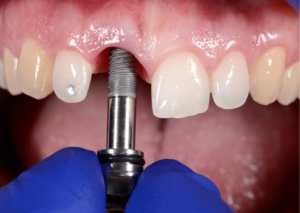

يتم إجراء عمليات الزرع في مراكزنا من قبل فريق من أخصائي زراعة الأسنان ذوي المهارات العالية وأطباء الأسنان التجميليين للحصول على دقة جراحية متميزة وجماليات ممتازة للابتسامة

يترأس مراكزنا فريق مختار بعناية من خبراء زراعة الأسنان. وبعد عملية الزرع يتم تركيب التيجان والجسور ، والتي يتم تصميمها بأقصى قدر من الدقة والجمالية لمنحك الابتسامة المثالية.